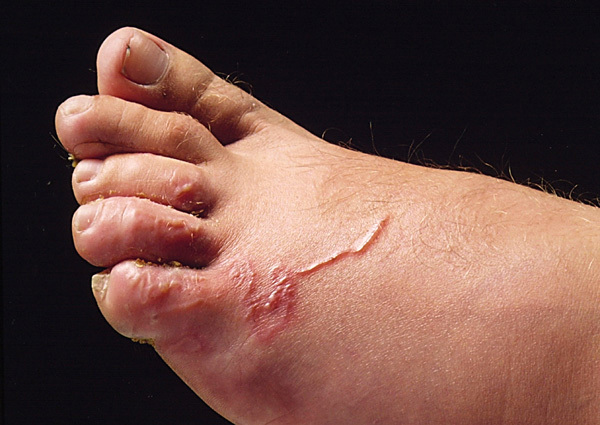

Qu’est ce que c’est?

Ostéite du 2e orteil. Fistule pathognomonique